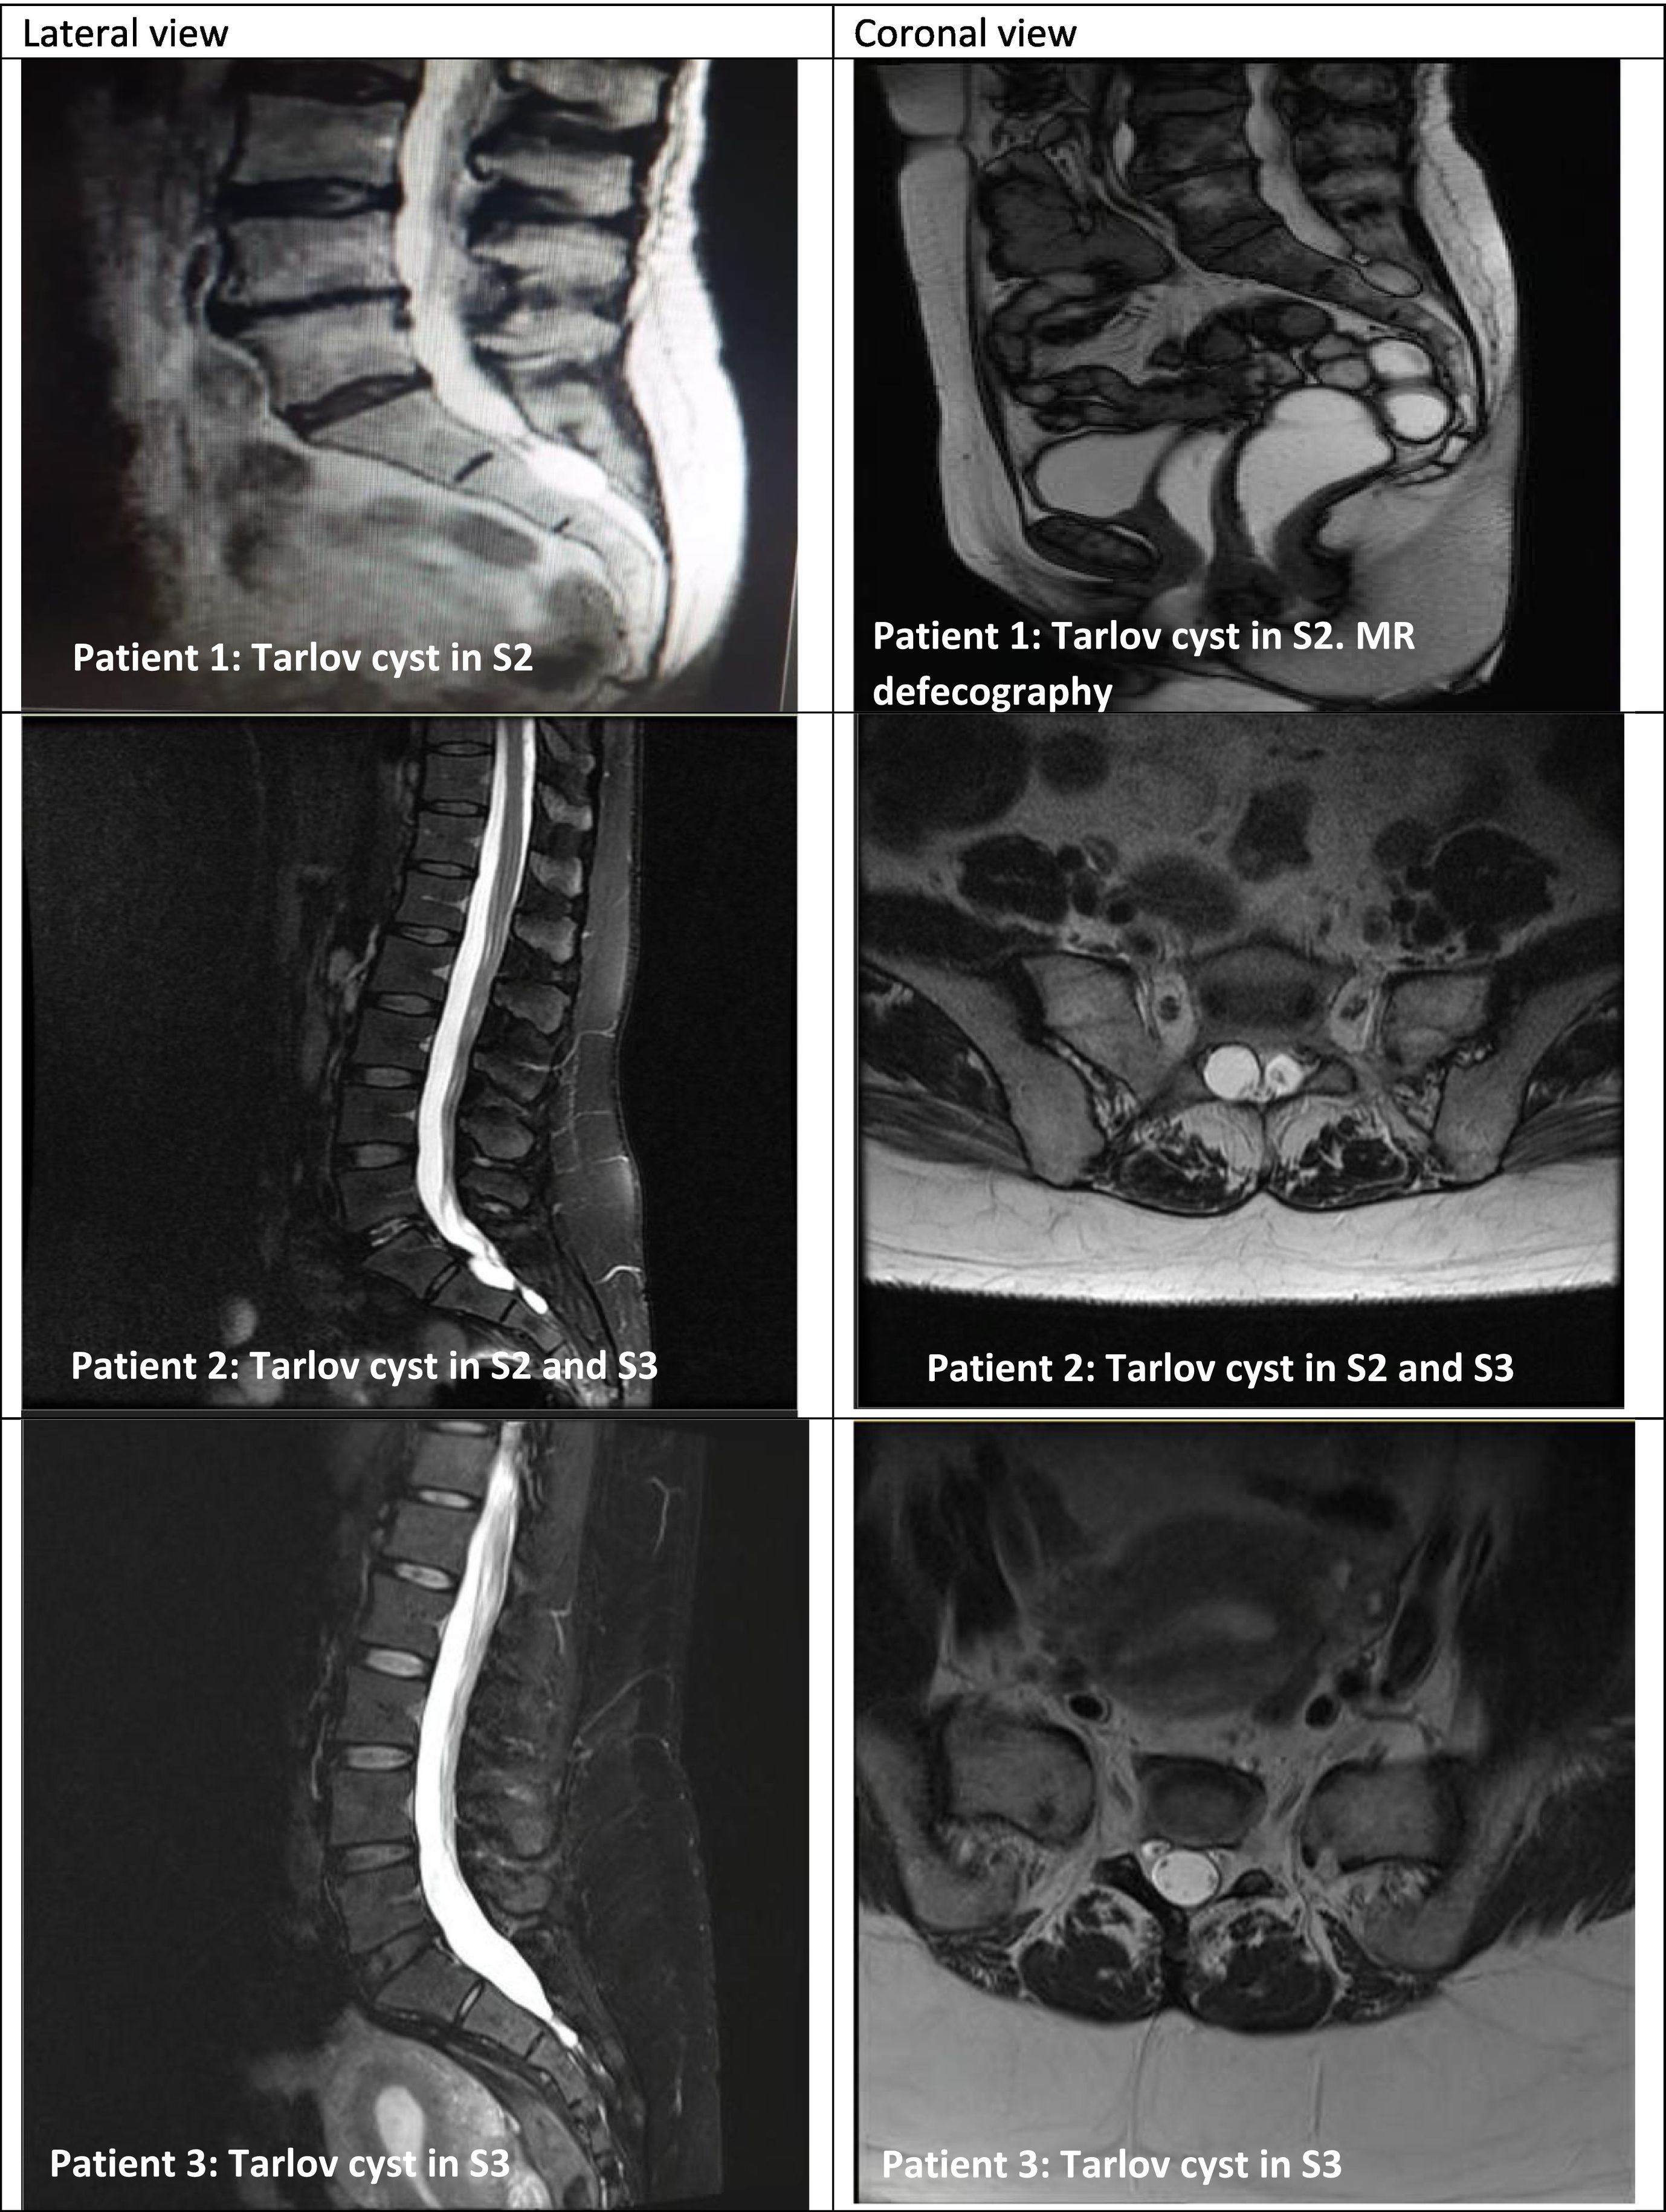

Reverse Tarlov Cyst Symptoms Naturally: A Powerful Diet Plan